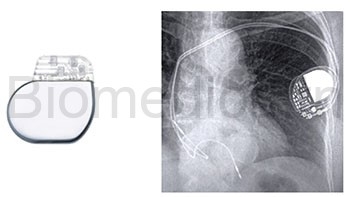

Le plus petit stimulateur cardiaque à double chambre au monde constitue un exemple remarquable d'innovation médicale, démontrant sa durabilité inébranlable.

Les stimulateurs cardiaques sont des appareils utilisés pour réguler et stabiliser le rythme cardiaque.

Pour rétablir un rythme cardiaque régulier, une stimulation électrique est émise par un stimulateur cardiaque. Les stimulateurs cardiaques pèsent actuellement environ 28 g et ont une taille comparable à une pièce de 2 euros.